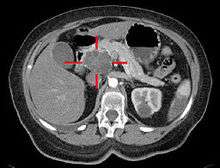

Medical imaging techniques, such as computed tomography (CT scan) and endoscopic ultrasound (EUS) are used both to confirm the diagnosis and to help decide whether the tumor can be surgically removed (its "resectability").[5] Magnetic resonance imaging and positron emission tomography may also be used,[4] and magnetic resonance cholangiopancreatography may be useful in some cases.[28] Abdominal ultrasound is less sensitive and will miss small tumors, but can identify cancers that have spread to the liver and build-up of fluid in the peritoneal cavity (ascites).[5] It may be used for a quick and cheap first examination before other techniques.[42]